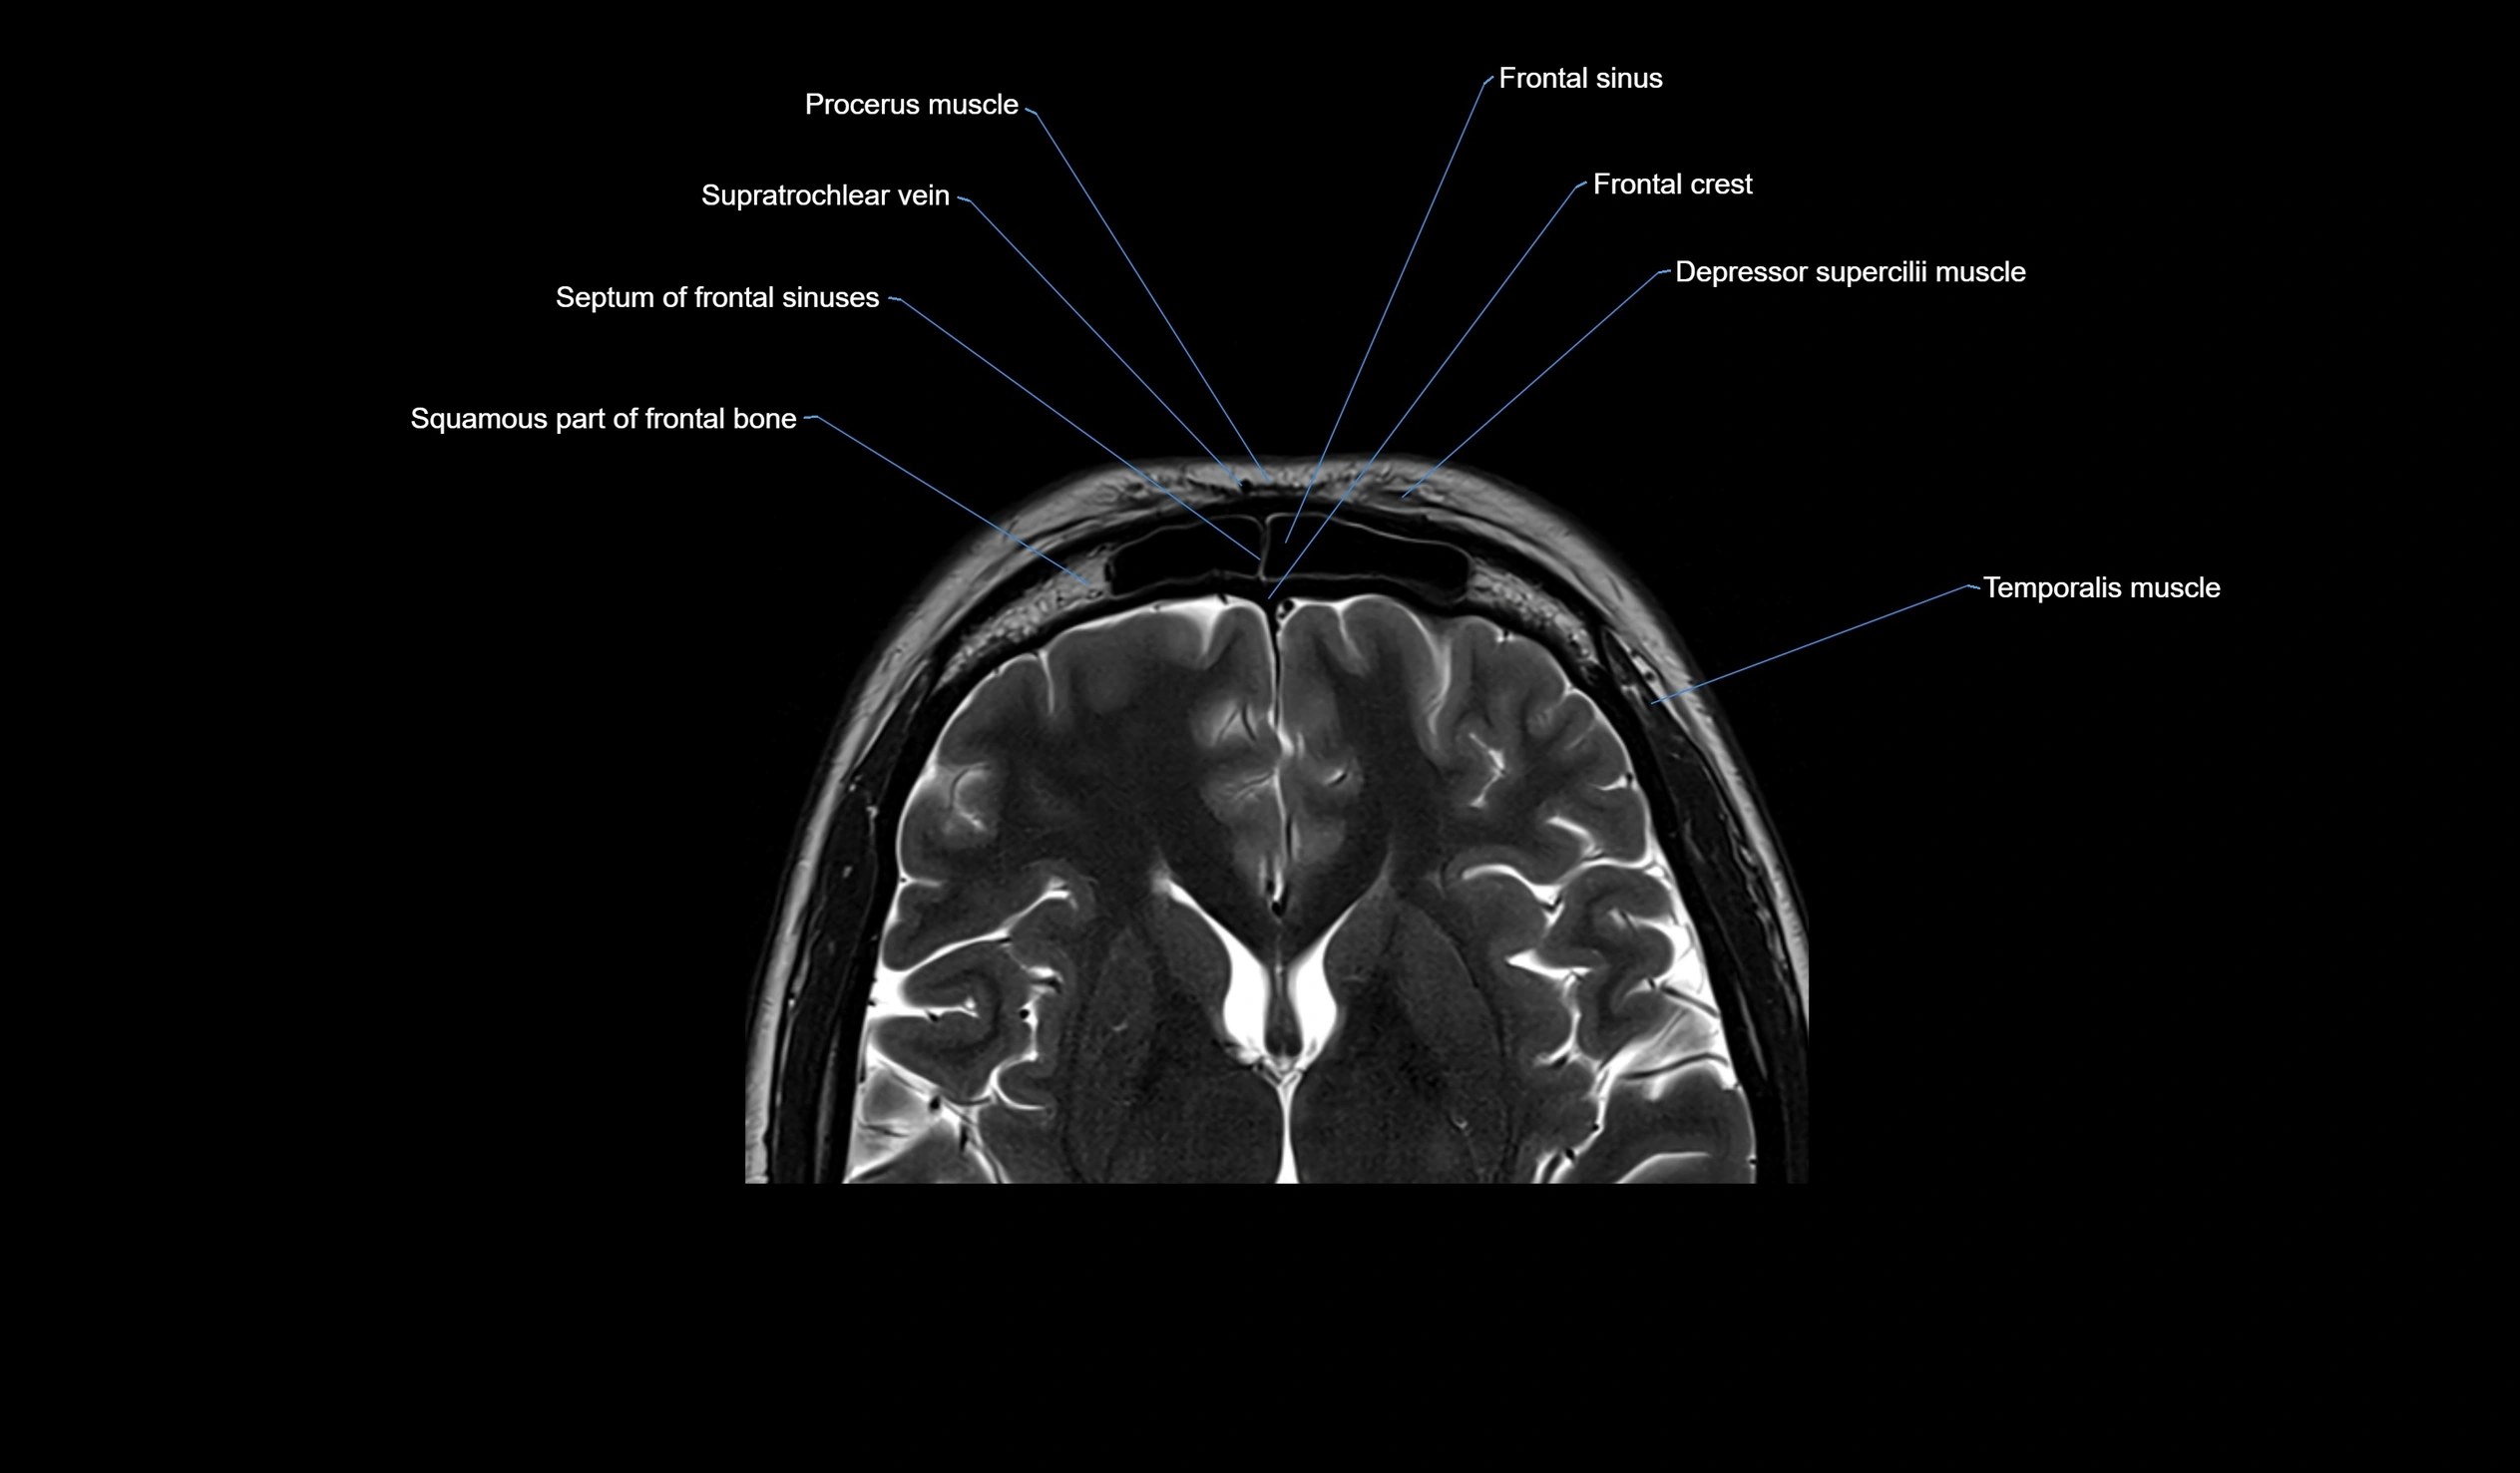

MRI images